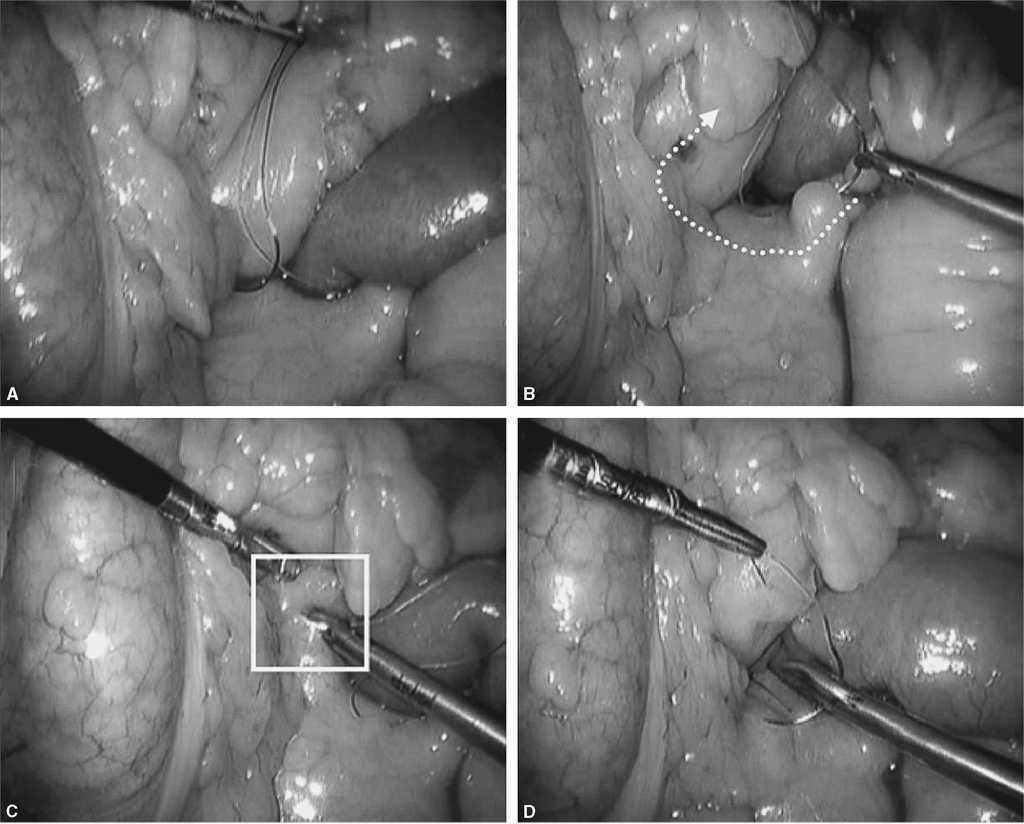

Fig. 6. El objetivo ahora es seguir con la sutura continua por ambos lados del asa Y de Roux cerrando el espacio de Petersen y ojal de mesocolon transverso haciendo una corbata. A: cómo se hace con la sutura 1 el cierre del meso en el lado izquierdo. B: es importante para este propósito coger la serosa intestinal y tejido graso del meso. C: en el cuadrado blanco se aprecia que la sutura avanza y coge serosa intestinal. D: una vez llegado a la mitad se deja la sutura y avanzaremos la sutura 2 desde el otro lado hacia la sutura 1.

Fig. 7. A: identificamos la sutura 2 y preparamos el campo para comenzar la hemicorona desde el lado derecho al izquierdo hasta encontrarnos con la sutura 1. B: se realiza plicatura del meso con una sola pasada de la aguja y se asciende. Aquí estamos cerrando el espacio de Petersen desde el lado derecho del asa Y de Roux. C: se avanza hasta encontrar la sutura 1 en el punto medio, cogiendo serosa intestinal y grasa del mesocolon (cuadro blanco). D: cuando se realiza tracción del hilo (Ethibond®), se plica el meso cerrando el espacio de Petersen.